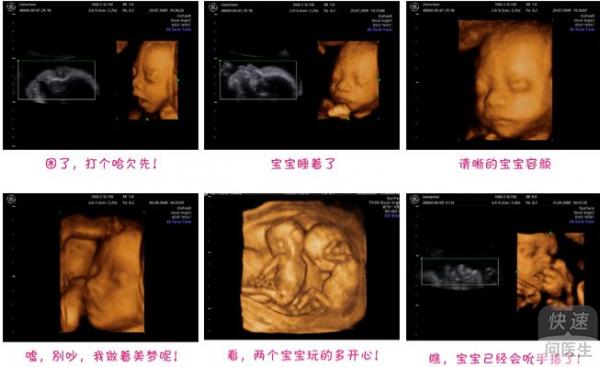

当女性在怀孕期间,一般都要做孕检,经过一系列检查,如血常规检查、孕激素检查、B超检查、心脏彩超检查等项目,做这些检查都有固定的时候,并不是什么时候做都可以,做的越多越好,那么怀孕几个月做彩超比较合适呢?下面就为大...